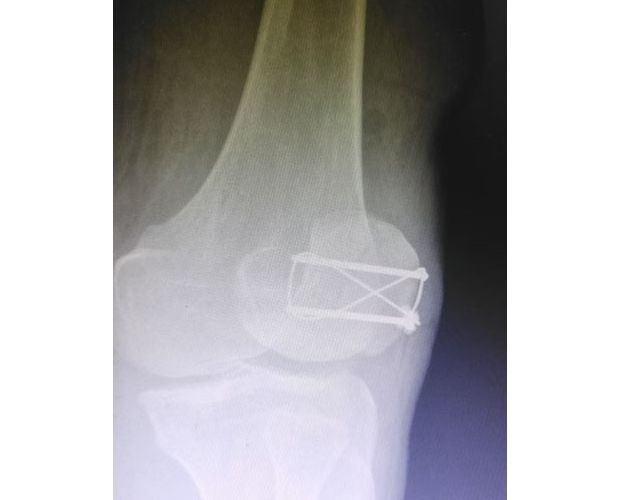

该患者因意外外伤导致髌骨骨折后,紧急前往何店镇中心卫生院就诊。该院外科医护团队迅速响应、规范处置,第一时间为患者完善各项术前检查,全面细致评估患者身体状况及骨折伤情,精准把握手术指征。为最大限度保障手术安全与治疗效果,切实减少患者往返城区医院的奔波之苦,降低就医成本,该院立即启动医共体专家协作机制,正式向曾都区人民医院申请专家技术支持。接到申请后,徐三军主任快速响应、主动下沉,带着丰富的临床经验和精湛的手术技术赶赴卫生院,与该院外科医护团队深入研讨,结合患者具体病情制定个性化手术方案,细致梳理术前各项准备工作,为手术顺利开展筑牢坚实基础。

手术现场,徐三军主任凭借多年积累的临床经验和娴熟的手术技巧,精准完成骨折复位、钢板内固定、伤口缝合等一系列关键操作,动作规范流畅、精准高效,最大限度减少手术创伤。该院外科医护团队全程密切配合、协同发力,严格按照手术规范操作,全程严密监测患者心率、血压等生命体征,及时应对术中各类突发情况,全力保障手术安全。此次手术全程顺利,术中出血量少,患者生命体征始终平稳,术后患者顺利安返病房,为后续康复治疗奠定了坚实基础。